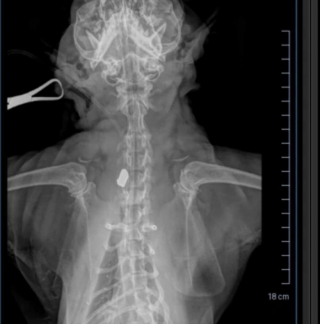

En y regardant de plus près, Jen a vu qu’il avait une blessure au cou, et l’a emmené chez le vétérinaire. Les analyses ont montré que le chat avait été blessé par arme à feu, et que la balle était toujours logée dans son cou. L’intervention chirurgicale était particulièrement chère, et Jen n’avait pas les moyens de la payer.

OJ a été opéré avec succès, et la balle a été retirée. Il a ensuite rejoint la famille qui était sur le point de l’adopter et qui a pu finaliser les procédures. Sur place, il s’est remis de sa blessure et de l’opération, entouré d’amour et de bienveillance.